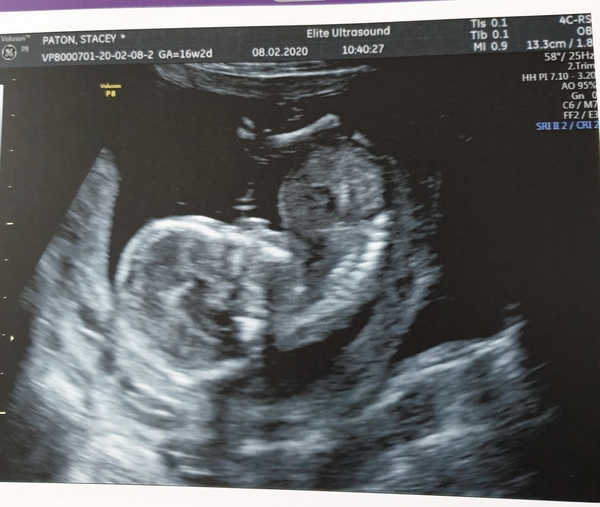

So we got the scan and the balloon my DS popped it and it's a Girl! She was trying to do a forward roll in the scan photo haha!